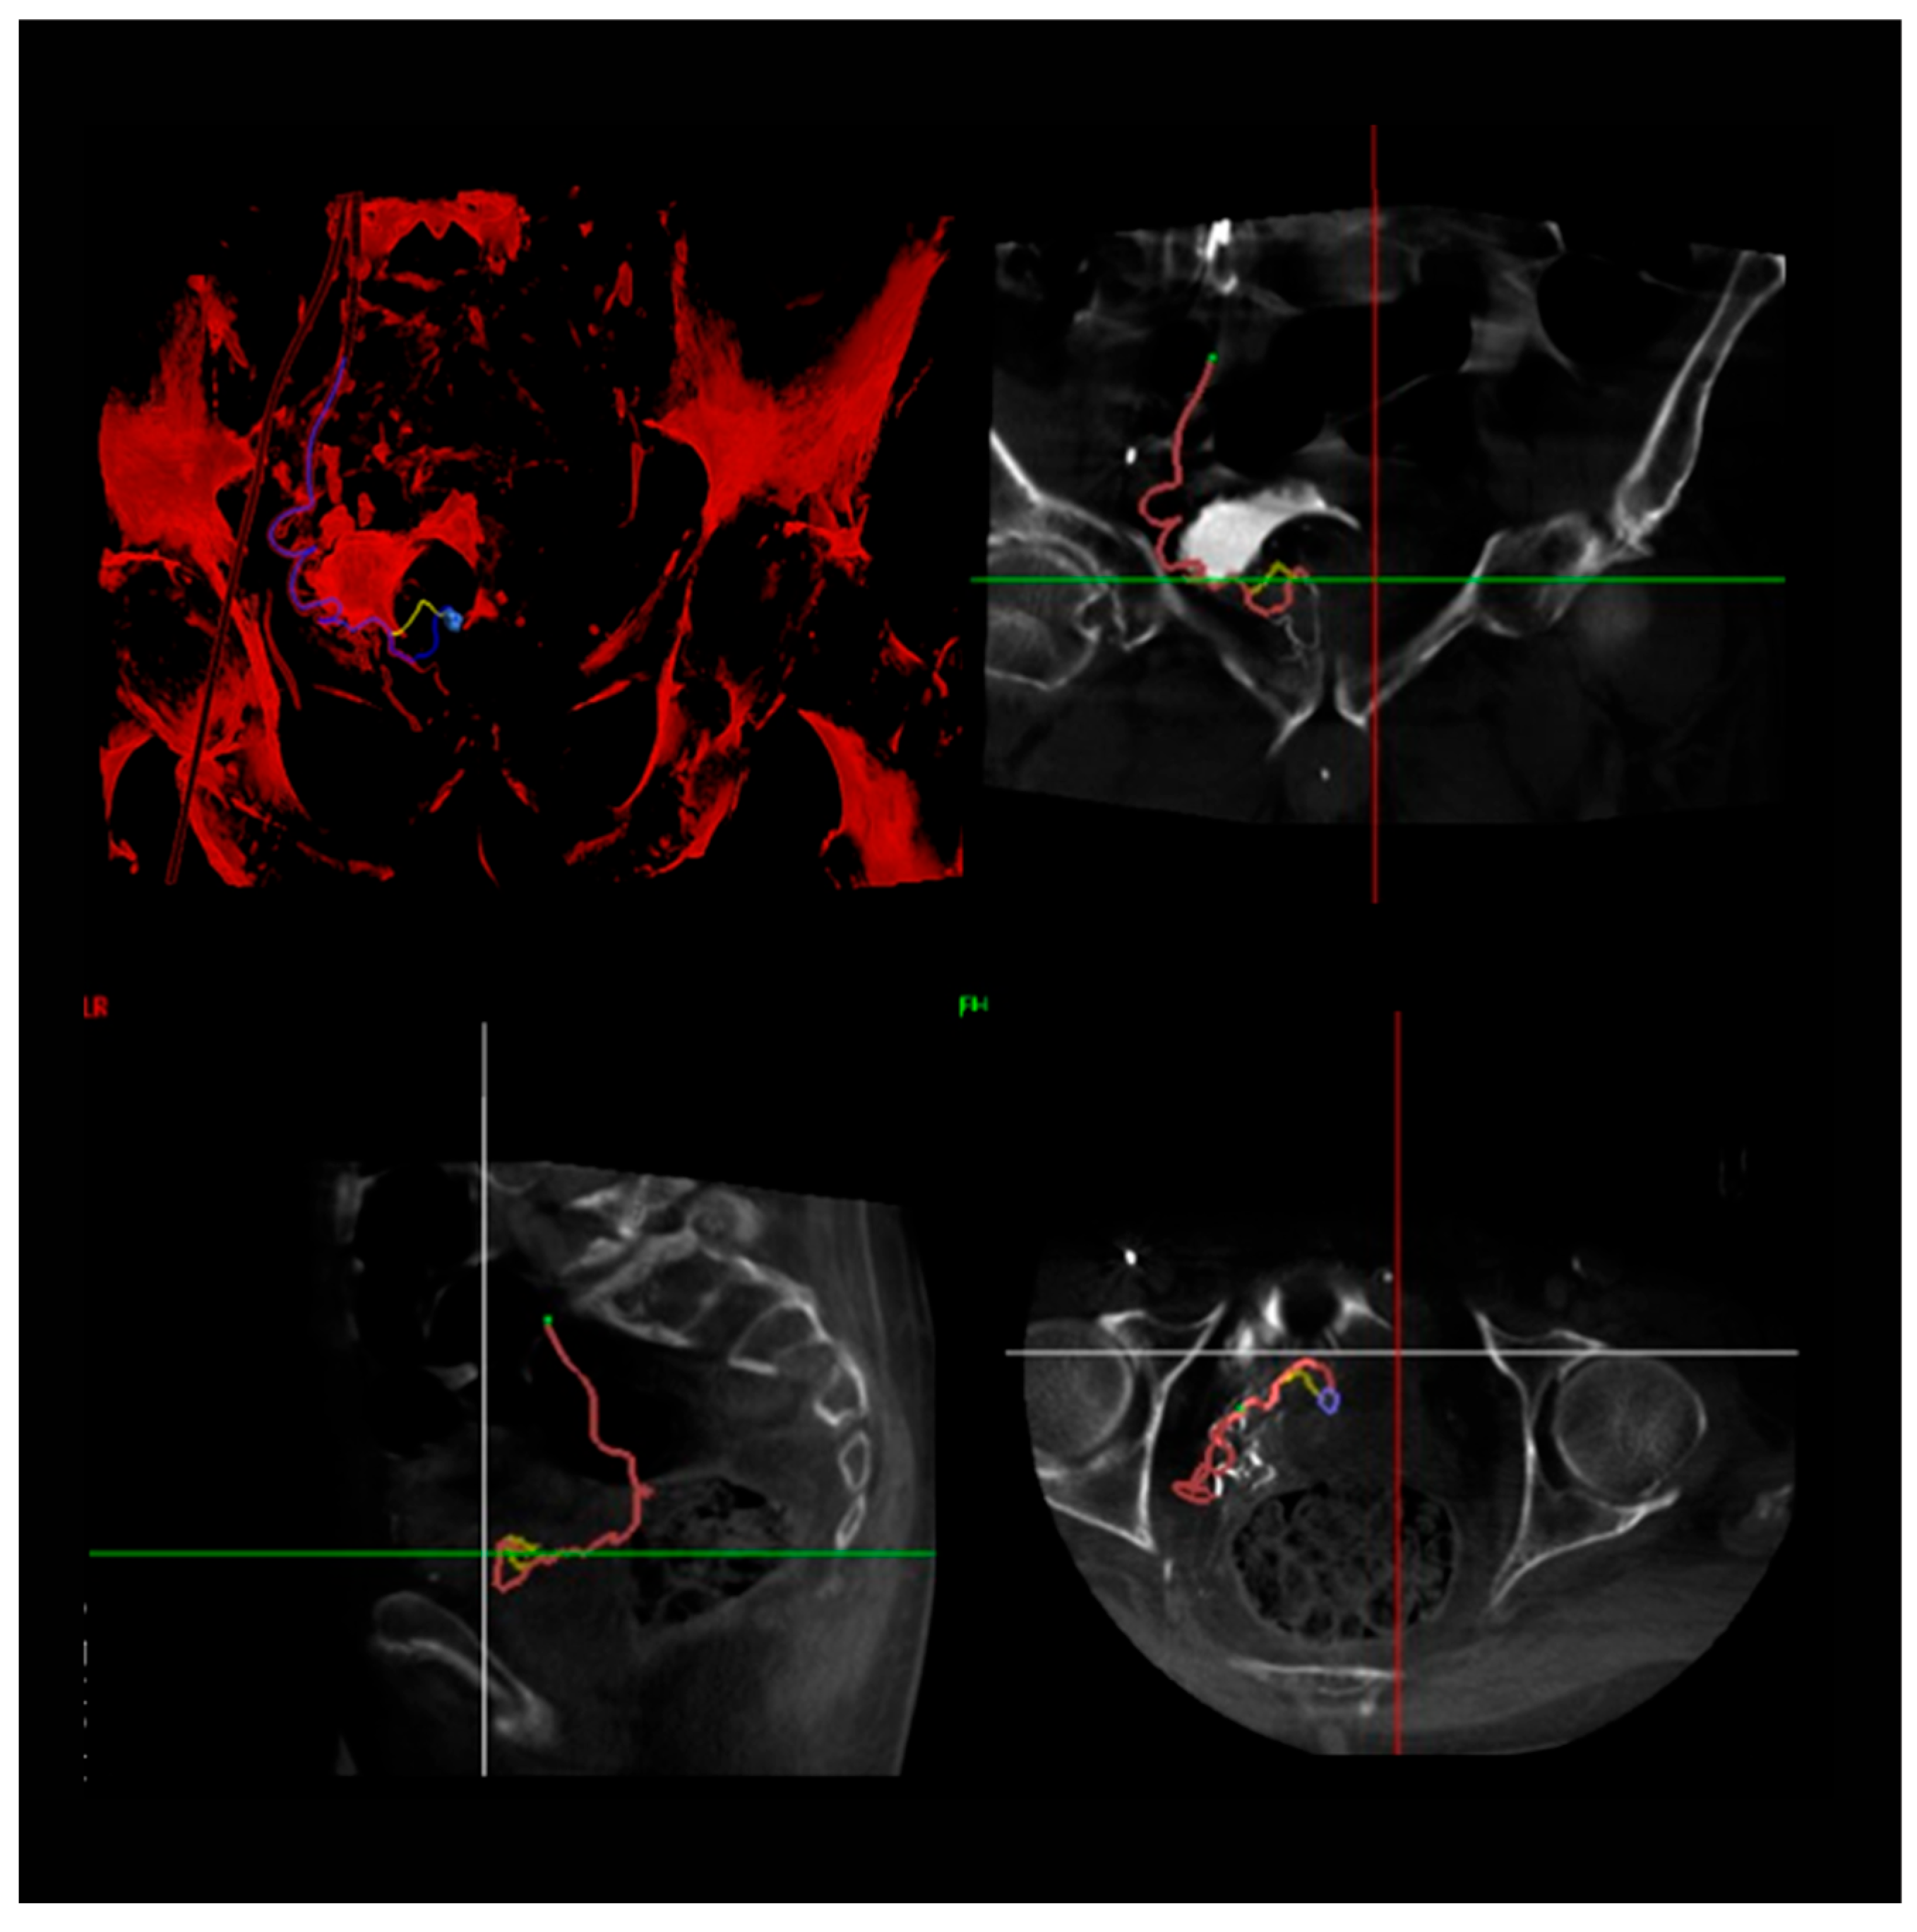

2.3.1. Arterial Access and Imaging

2.3.2. Catheterization and Embolization

2.3.3. Post-Procedure Imaging and Verification